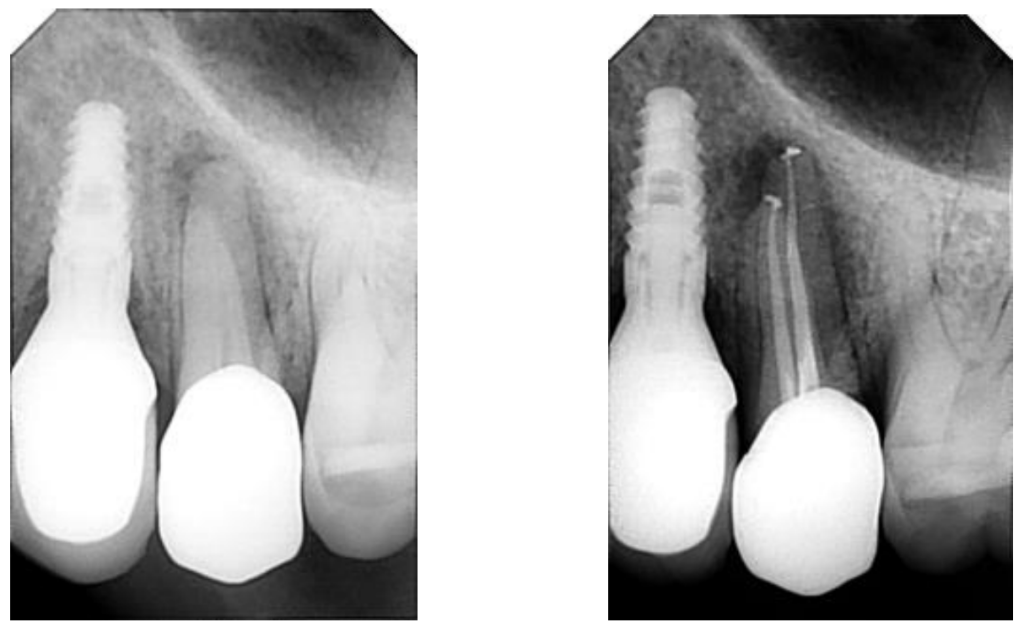

Case Study: Endodontics - Root Canal Treatment

Before: The patient was diagnosed with asymptomatic apical periodontitis in multiple teeth. The condition showed radiographic signs of infection at the root apex, though without significant pain at the time of diagnosis.

Treatment: A complete root canal therapy was performed using advanced instrumentation (WaveOne Gold system), active irrigation protocols, and biocompatible sealing materials. This ensured thorough cleaning, disinfection, and sealing of the canals to prevent reinfection.

After: The final radiograph shows well-sealed canals and elimination of the infected tissue. This treatment preserved the natural teeth, relieved the risk of future pain, and restored full dental function — avoiding the need for extraction and maintaining the patient’s oral health.

Case Study: Endodontics - Root Canal Therapy

Before: The patient presented with symptomatic apical periodontitis, showing infection at the root tip and discomfort when chewing. Radiographic analysis confirmed the need for endodontic treatment to eliminate the infection and preserve the tooth.

Treatment: Root canal therapy was carried out using modern techniques, including advanced rotary instrumentation (WaveOne Gold), active irrigation solutions (NaOCl, EDTA), and biocompatible sealing with AH Plus resin. This ensured complete cleaning, disinfection, and sealing of the canals.

After: The final radiograph demonstrates a properly sealed root canal, elimination of the infected tissue, and restoration of tooth stability. The treatment successfully relieved pain, saved the natural tooth, and protected the patient from future complications.